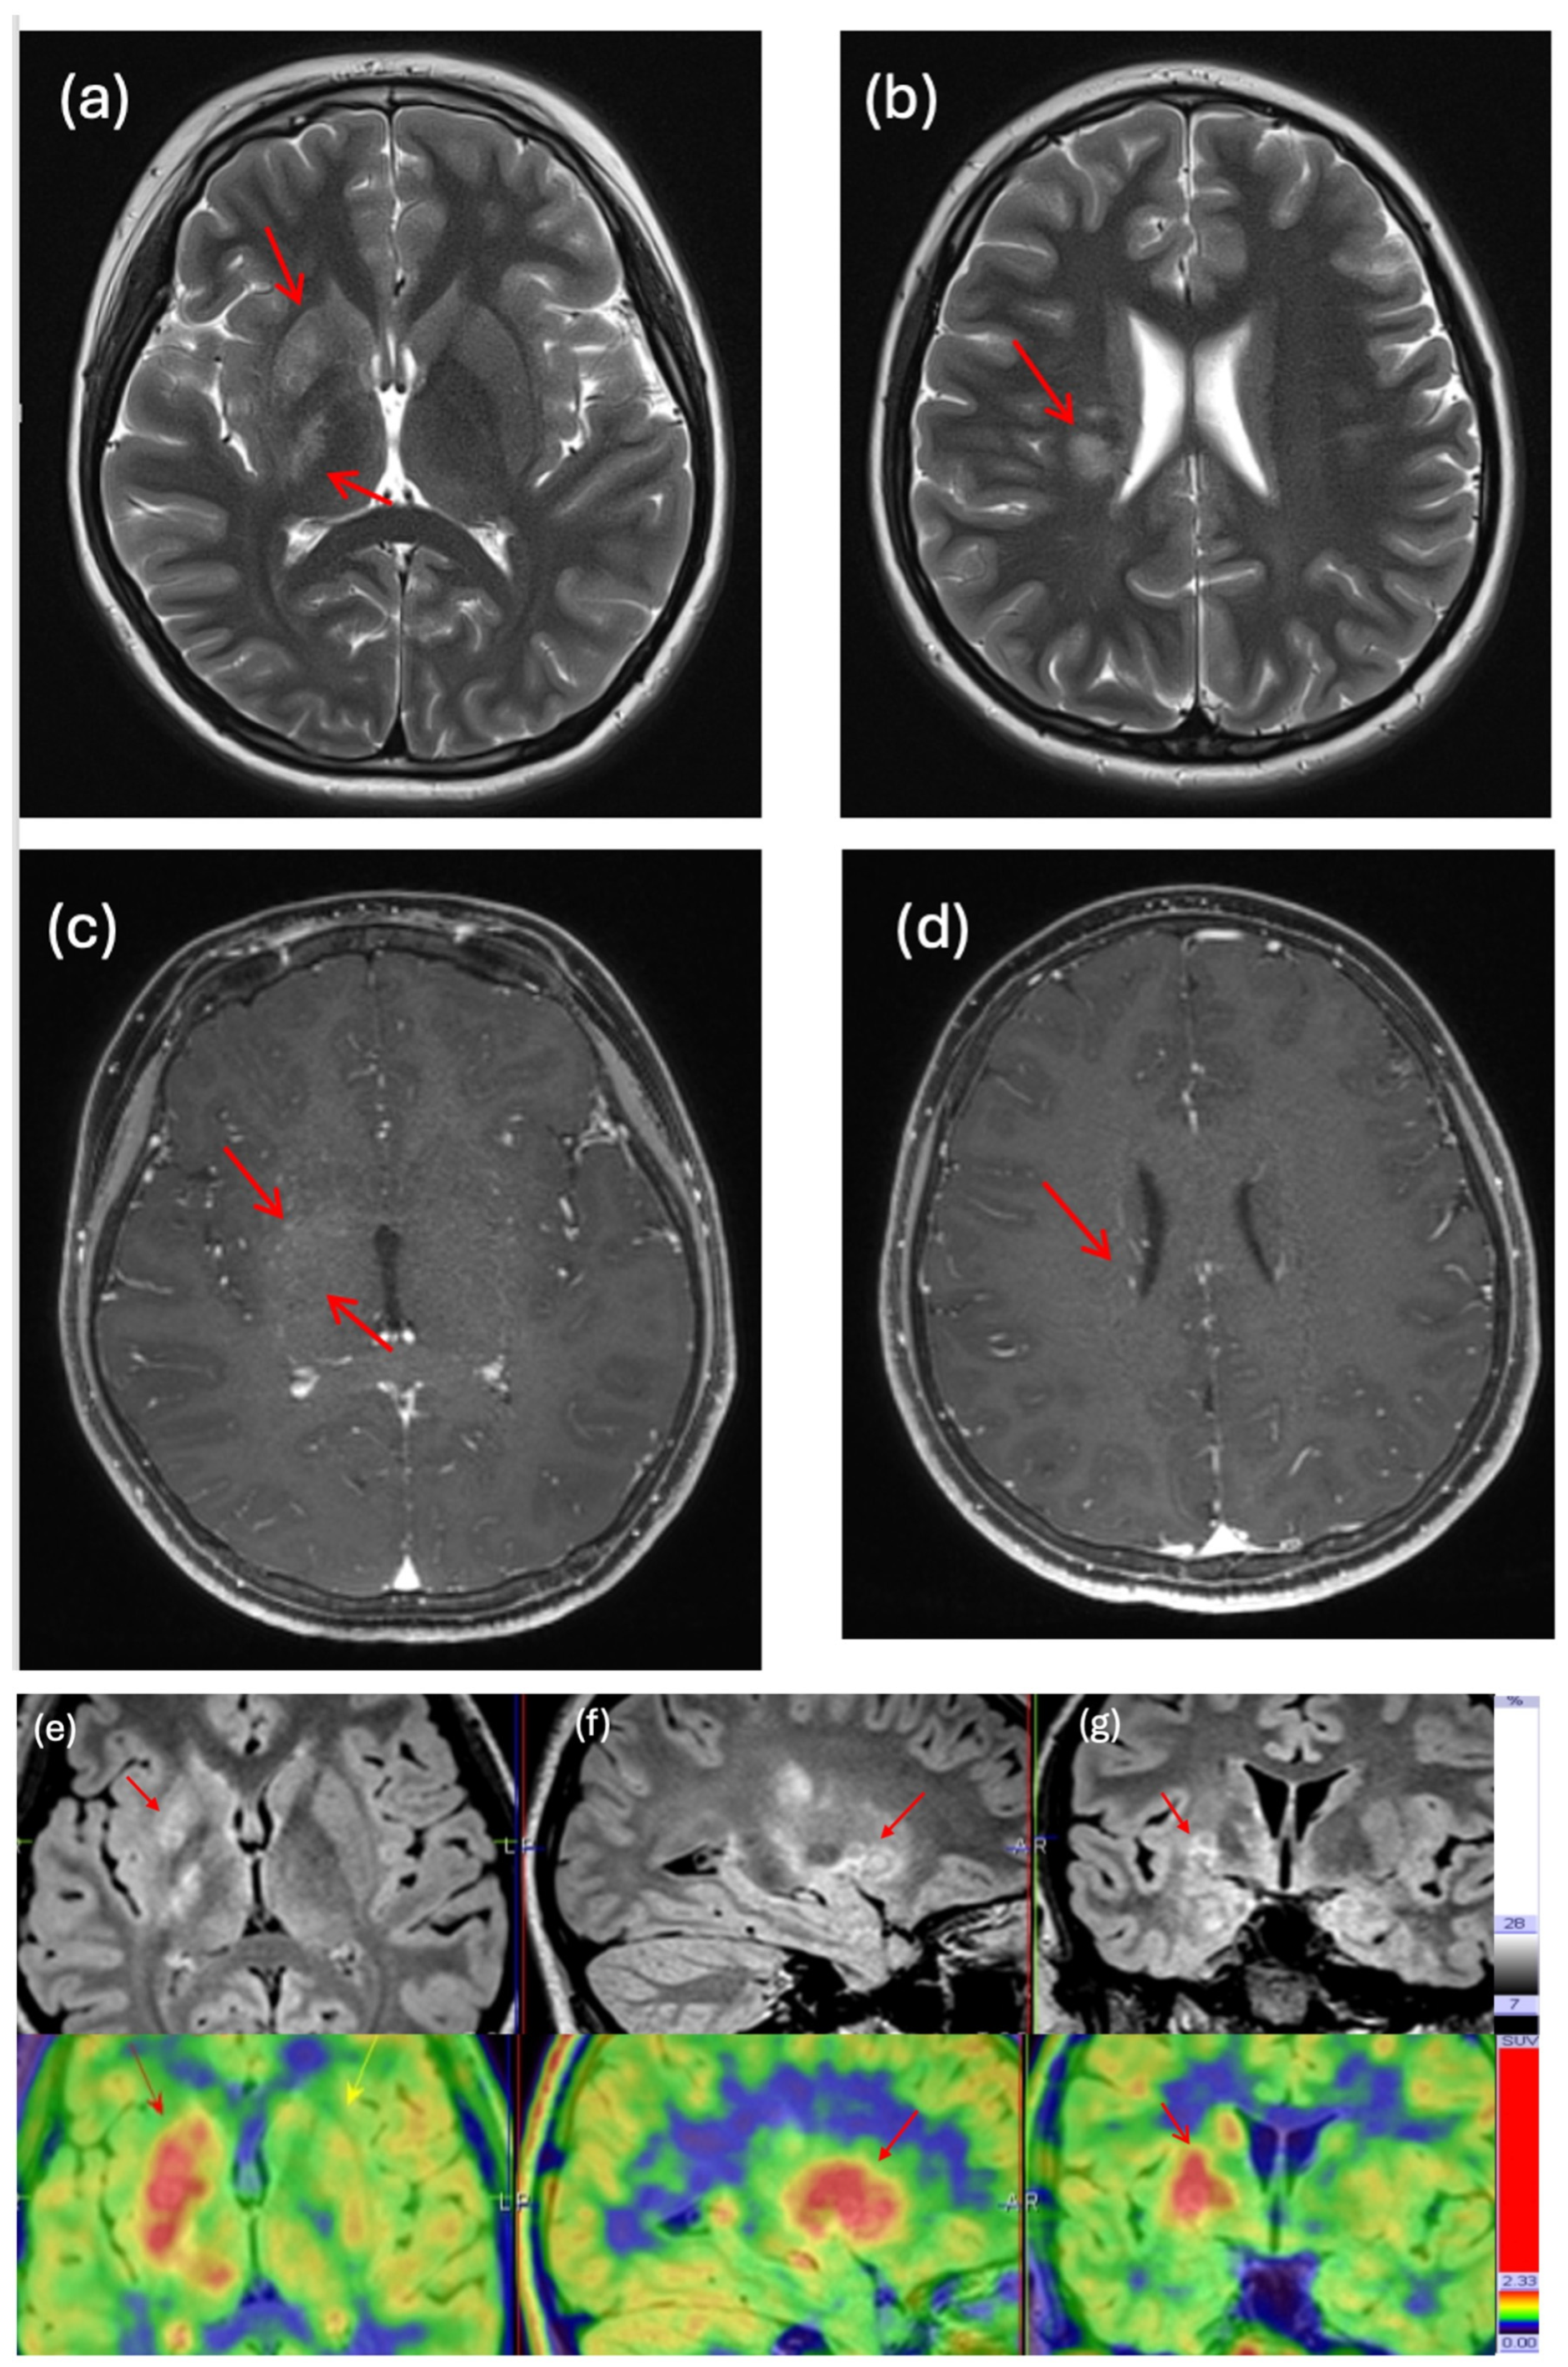

| 3 | 11 | M | Germinoma | Basal ganglia | Diagnosis | MET | 3 | 1.78 | First MRI suggestive of infarction; high MET uptake on PET-MRI suggestive of high-grade neoplasm. |

| 14 | 11 | M | Germinoma | Suprasellar and pineal | Diagnosis | FET | 2.56 | 1.9 | First MRI identified only the pineal lesion; PET-MRI showed high metabolic uptake over suprasellar region and pineal region; diagnosis of bifocal germinoma made after histological confirmation of suprasellar lesion. |